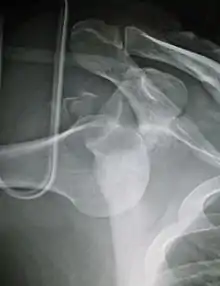

| Anterior dislocation of the left shoulder. | |

In over 95% of shoulder dislocations, the humerus is displaced anteriorly.[6] In most of those, the head of the humerus comes to rest under the coracoid process, referred to as sub-coracoid dislocation. Sub-glenoid, subclavicular, and, very rarely, intrathoracic or retroperitoneal dislocations may also occur.[7]

Anterior dislocations are usually caused by a direct blow to, or fall on, an outstretched arm. The person typically holds his/her arm externally rotated and slightly abducted.

An anterior dislocation of the shoulder